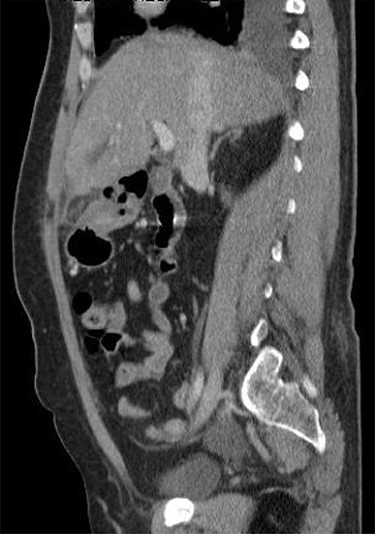

A 53-year-old fit and well woman presented to the emergency department with acute epigastric and right hypochondrium pain with a positive Murphy’s sign of the abdomen. The patient was anicteric and apyrexial. Blood tests performed revealed a white cell count of 13.6 × 109/L and a C-reactive protein of 110 U/L. Liver function tests, amylase and urea and electrolytes were unremarkable. A working diagnosis of acute cholecystitis was made and the patient commenced on intravenous fluids and intravenous antibiotics. Abdominal ultrasound was performed, which demonstrated no gallstones nor choledocholithiasis and was essentially normal. Given the raised inflammatory markers and persistent abdominal pain, CT scan was performed (Fig. 1). This revealed a 32 × 22-mm oval-shaped fat density lesion with peripheral hyper attenuation adjacent to the falciform ligament, representing intraperitoneal focal fat infarction of the fatty appendage of falciform ligament. Sagittal reconstruction showed a central hyperdense thrombosed vessel secondary to torsion of the falciform ligament (Fig. 2).

Sagittal reconstruction redemonstrates central hyperdense thrombosed vessel secondary to torsion